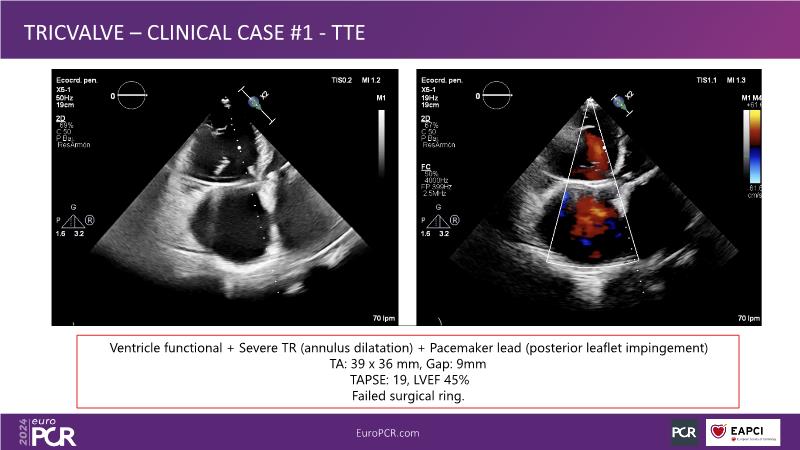

Watch this session to gain comprehensive insights into the use, safety, and efficacy of heterotopic tricuspid valves. Learn to identify ideal candidates with severe tricuspid regurgitation, understand key procedural factors for successful implantation, and receive tips on valve systems and anatomy. The session also includes a recorded TricValve case, discusses the current status of transcatheter tricuspid valve therapies, and explores the placement of heterotopic tricuspid valves in the guidelines.